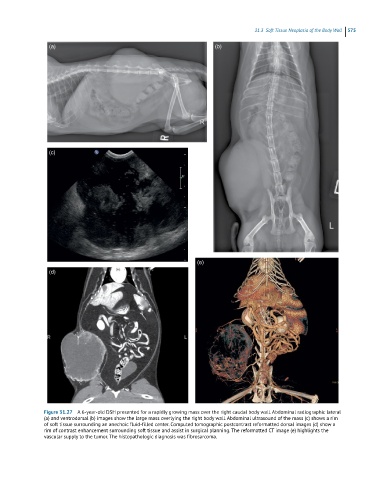

Figure 31.27 A 6-year-old DSH presented for a rapidly growing mass over the right caudal body wall. Abdominal radiographic lateral

(a) and ventrodorsal (b) images show the large mass overlying the right body wall. Abdominal ultrasound of the mass (c) shows a rim

of soft tissue surrounding an anechoic fluid-filled center. Computed tomographic postcontrast reformatted dorsal images (d) show a

rim of contrast enhancement surrounding soft tissue and assist in surgical planning. The reformatted CT image (e) highlights the

vascular supply to the tumor. The histopathologic diagnosis was fibrosarcoma.